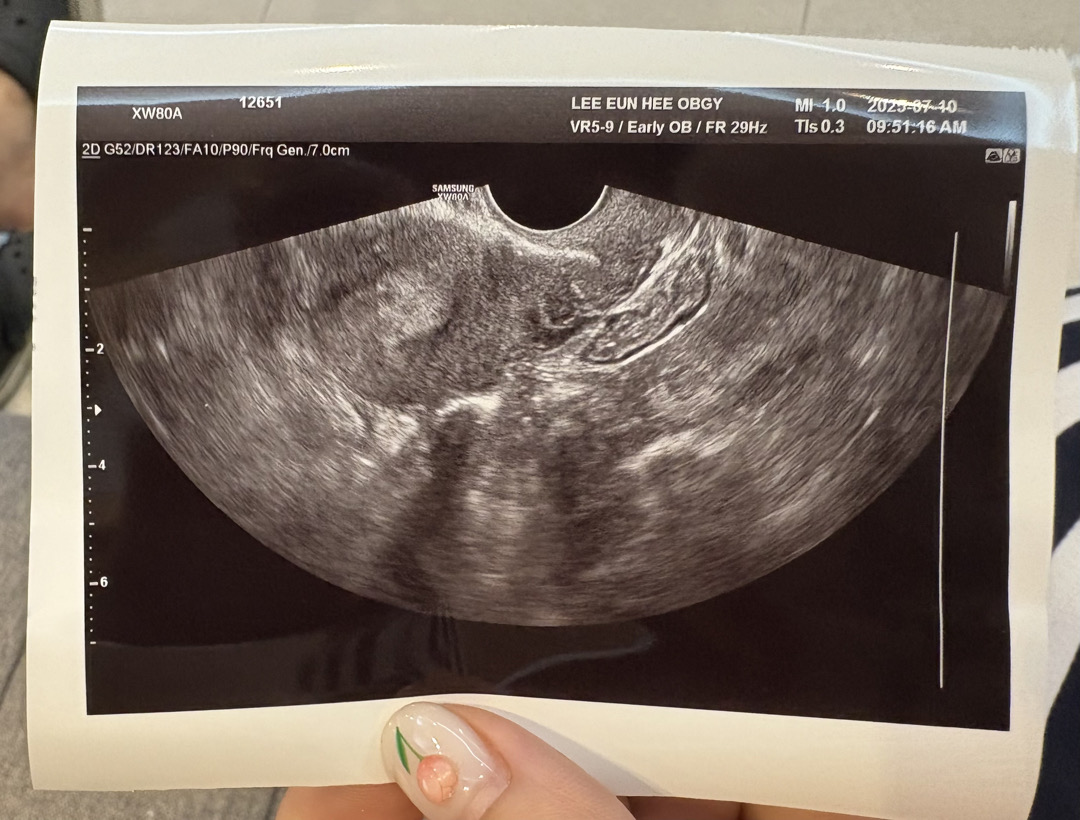

피검1차후 드뎌 아기집보고왔어요!!!

1차피검 98.** 나오고 일주일뒤어 초음파보자하셔셔 내심 이래저래걱정도되고 임신확정도아니라서 넘떨리드라구요… 첫째도 시험관한번에되서 출산까지 실감이안났는데 둘째는 더 실감이안나는것같아요…. 막생기준으로보면 5주차라고 생각했는데 막상가서보니 4주 1일차드라구요 요번엔 제발 아무탈없이 출산까지갔으면 하는바램입니다!!!